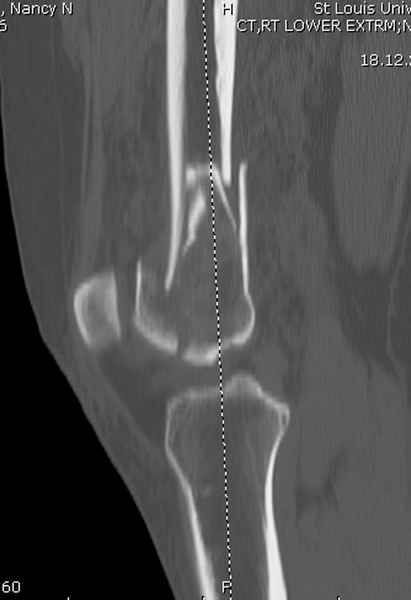

Re: Сегментарный перелом бедра - открыто или закрыто?

При наличии различных имплантов, любые варианты: слева (полу) открытым - мининвазивным, а справа закрытым интрамедуллярным методом, его считаем более чем приемлемым для фиксации данных переломов.

Проксимальная и дистальная блокировка, независимо от техники введения штифта, ретроградно или антеградно, гарантирует сращение сегментарных переломов бедра без укорочения. Штифты диаметром 12 мм с блокировкой сверху и вниз двумя шурупами выдерживают вес 75 кг больного, что позволяет раннюю профилактику контрактур.

Погоня за "красивой рентгенограммой" не всегда оправдана для фиксации кости, где имеется массивное мягкотканое покрытие. Если так уж хочется исправить положение кости, то при наличии ЭОП, большие костные фрагменты могут быть развернуты или приближены к основному фрагменту методом применения Joystick.

Главное в лечении сегментарных переломов - необходима осторожность при рассверливании канала, продвижение гибкого сверло через сегмент проводят без сверления, толканием, а то были случаи, когда весь сегмент крутился вместе со сверлом.